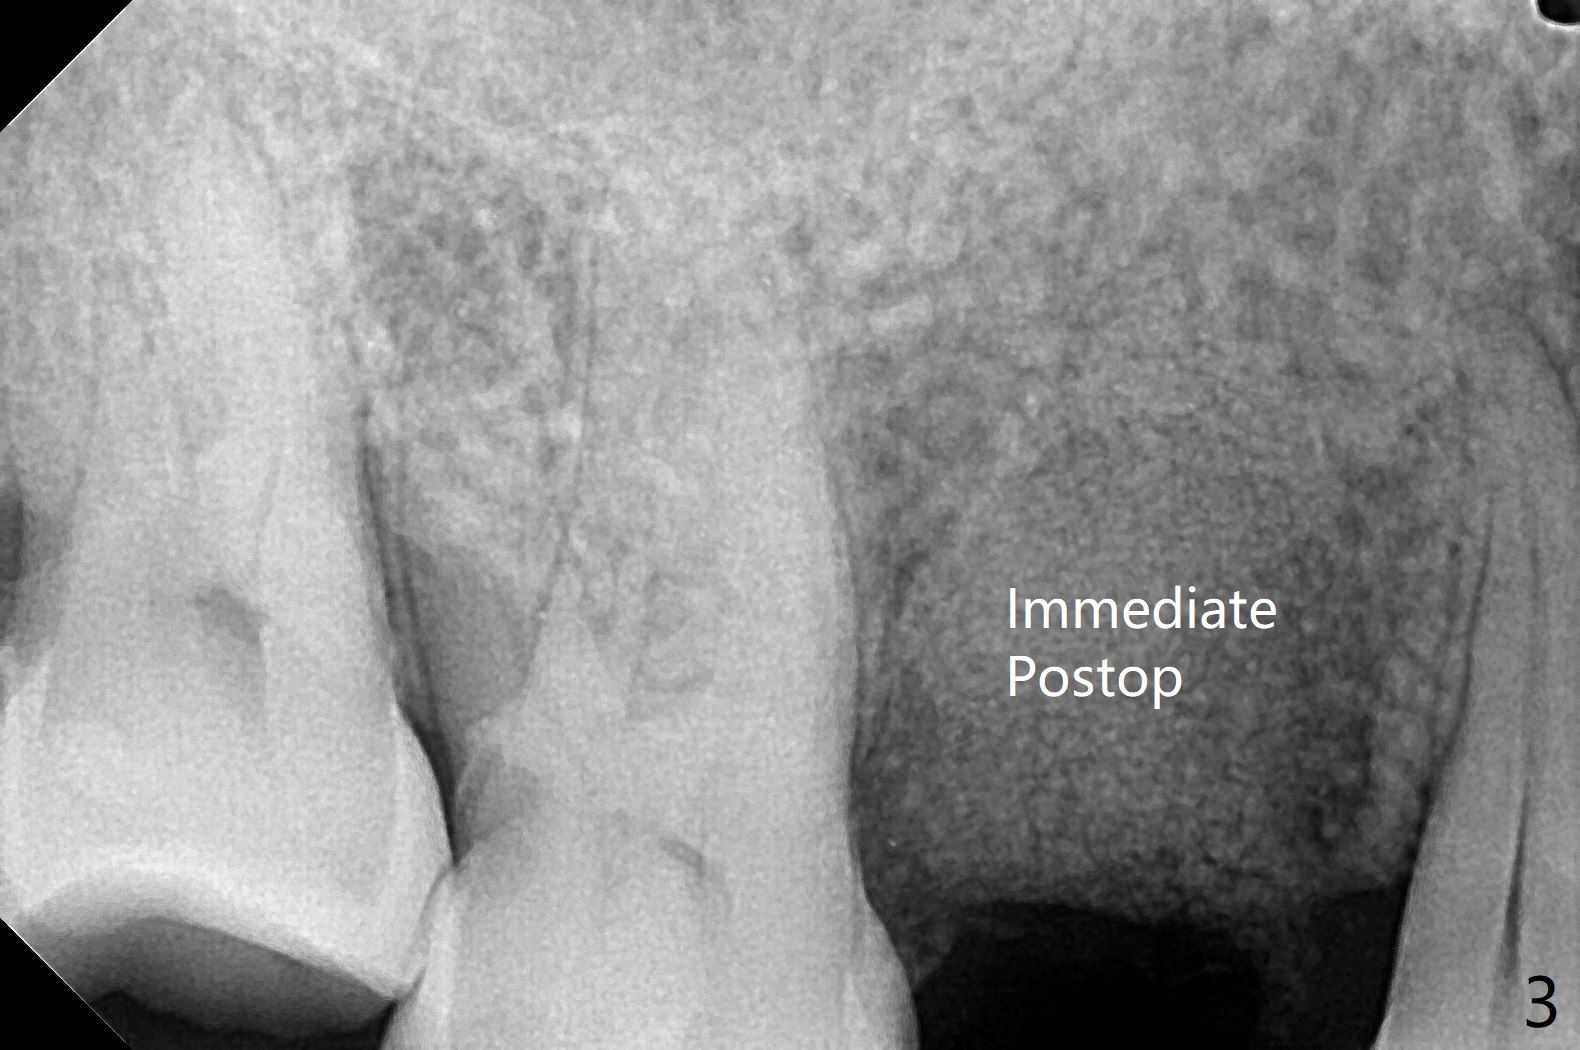

61岁女,右下六缺失,要求拔除纵裂右上五(图一:舌侧部分松动),刮除大量肉芽组织后,植入皮质骨骨粉(图二,三),覆盖6个月吸收膜,4-0 PGA 缝线,牙周敷料。